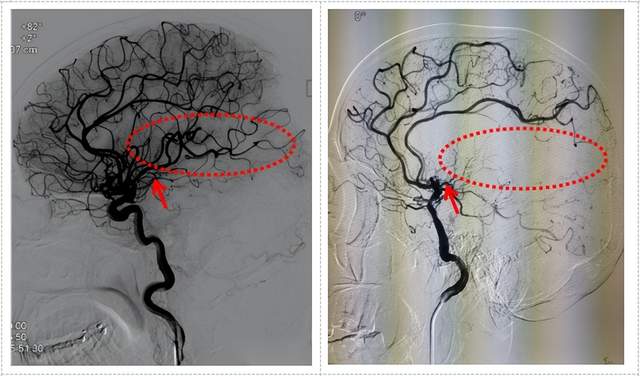

考虑到病情的凶险性,入院后,李凯还主任医师和李征副主任医师急诊为赵叔完善了脑血管造影检查,证实了赵叔颅内不仅长了多个动脉瘤,出乎意料的是还合并了烟雾病。这种情况对于已经68岁的赵叔来说可是雪上加霜。

术前DSA检查颅内多发动脉瘤

正常血管 烟雾病

面对该患者前交通动脉和右侧大脑前动脉多发动脉瘤合并烟雾病,无论是开颅动脉瘤夹闭还是血管内介入栓塞治疗难度都比较大。

手术过程顺利,通过一次手术为患者拆除了颅内二枚“炸弹”及烟雾病血运重建手术治疗。术后患者恢复顺利,精神、食欲逐步恢复正常,生活完全自理,取得了良好的治疗效果。